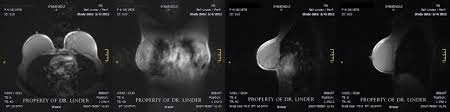

If you have silicone breast implants and suspect that an implant might have ruptured, talk to your plastic surgeon. When a rupture occurs your breast (s) will immediately deflate, usually within a day or two, and breast size will noticeably change. Nevertheless, your body will try to contain any silicone gel seeping in your breast tissue by forming a scar tissue around it, called "granulomas" or "siliconoma". Rupture can also cause capsular contracture. The relationship of free silicone to development or progression of disease is unknown. With silicone gel implants, you aren't able to physically see the appearance of a ruptured implant, whereas with saline implants, you will see a deflated breast with implant rupture. An imaging test, such as an mri or ultrasound, can show whether the implant has ruptured. What are the dangers of silicon? What is the life expectancy of silicone breast implants? Apr 01, 2019 · however, some may remain around the ruptured implant, and this can cause the fluid to change color. What are the risks of silicone implants? Silicone implant rupture that doesn't cause any noticeable symptoms is known as "silent rupture.". This makes is much more difficult to detect a rupture.

Aug 20, 2020 · pain, soreness or swelling. This makes is much more difficult to detect a rupture. If you have silicone breast implants and suspect that an implant might have ruptured, talk to your plastic surgeon. Nevertheless, your body will try to contain any silicone gel seeping in your breast tissue by forming a scar tissue around it, called "granulomas" or "siliconoma". An imaging test, such as an mri or ultrasound, can show whether the implant has ruptured. Changes in size or shape. What are the risks of silicone implants? What are the dangers of silicon? Silicone implant rupture that doesn't cause any noticeable symptoms is known as "silent rupture.". If you have saline breast implants and experience a rupture, you will immediately be aware of it. When a rupture occurs your breast (s) will immediately deflate, usually within a day or two, and breast size will noticeably change. The saline will leak from the outer silicone elastomer shell of your implant. With silicone gel implants, you aren't able to physically see the appearance of a ruptured implant, whereas with saline implants, you will see a deflated breast with implant rupture.

With silicone gel implants, you aren't able to physically see the appearance of a ruptured implant, whereas with saline implants, you will see a deflated breast with implant rupture. Light, clear fluid usually signals that the ruptured occurred within a month. Nov 14, 2013 · silicone breast implants can leak but do not deflate quickly the way saline implants do because the silicone gel is designed to stay in place when a leak occurs. An imaging test, such as an mri or ultrasound, can show whether the implant has ruptured. Changes in size or shape.